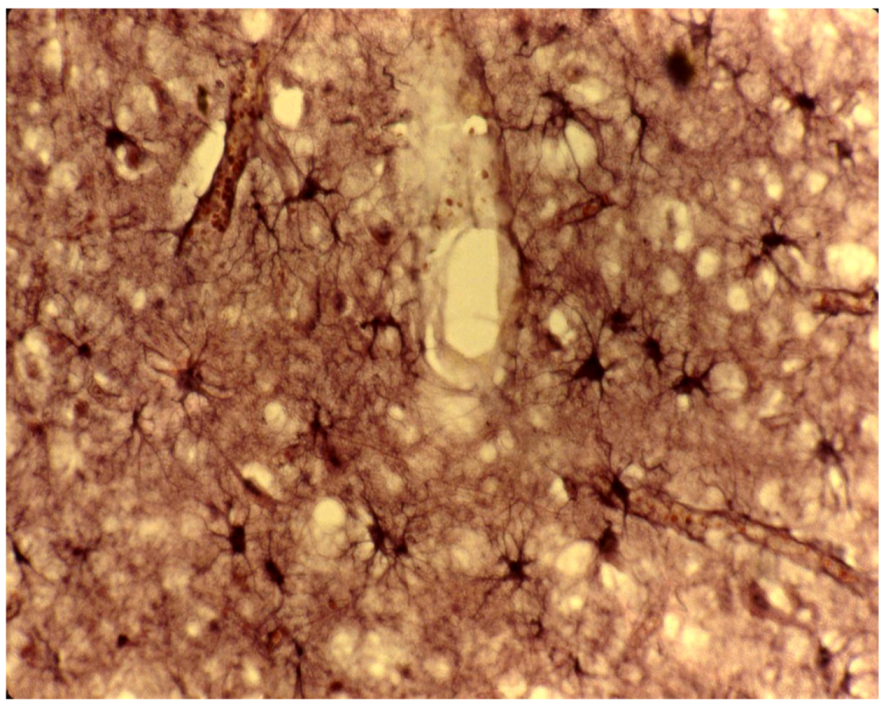

8. Neuropathology